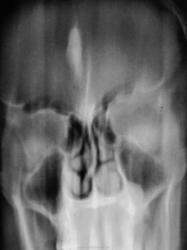

Пол пациента: Женский пол Тип патологии: Другое Область исследования: Челюстно-лицевая область и шея Методы исследования: Rg Томограммы гайморовых полостей. https://radiomed.ru/sites/default/files/styles/case_slider_image/public/user/12/2.p4180062a.jpg?itok=CsTi5YGN https://radiomed.ru/sites/default/files/styles/case_slider_image/public/user/12/3.p4180063.jpg?itok=-SEbP-QZ https://radiomed.ru/sites/default/files/styles/case_slider_image/public/user/12/4.p4180063a.jpg?itok=ggnObqVv ID:20675 Цель публикации: Консультация Ср, 18/04/2012 - 23:01 #1 Илья Юрьевич Не на сайте Был на сайте: 13 лет 9 месяцев назад Зарегистрирован: 25.03.2012 - 16:44 Публикации: 8 Киста (полип) в проекции нижнего носового хода слева, киста (утолщенная слизистая) в альвеолярной бухте левой верхнечелюстной пазухи. Чт, 19/04/2012 - 23:36 #2 doktor-rentgen Не на сайте Был на сайте: 9 лет 8 месяцев назад Зарегистрирован: 06.07.2010 - 20:56 Публикации: 640 А во лбу что? Пт, 20/04/2012 - 00:02 #3 Катенёв Валенти... Не на сайте Был на сайте: 7 лет 6 месяцев назад Зарегистрирован: 22.03.2008 - 22:15 Публикации: 54876 По всей видимости, обызвествленный фалькс церебри.

Киста (полип) в проекции нижнего носового хода слева, киста (утолщенная слизистая) в альвеолярной бухте левой верхнечелюстной пазухи.

По всей видимости, обызвествленный фалькс церебри.